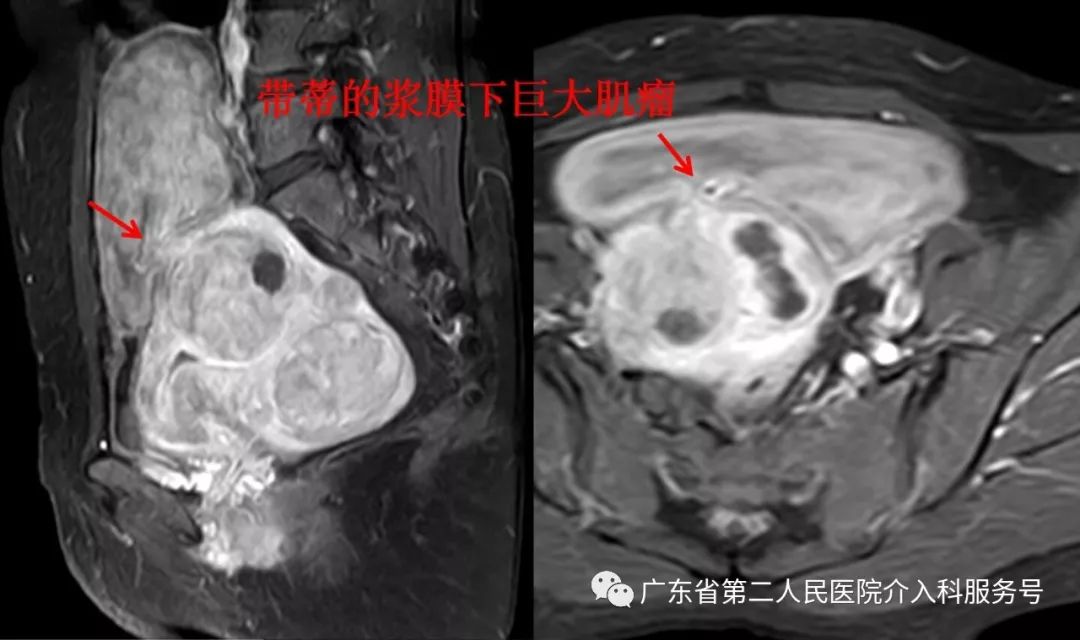

陈女士5年前月经量增多,去当地医院检查发现子宫多发肌瘤,因肌瘤较多、较大不能行腹腔镜肌瘤完全剔除,医生建议切除子宫治疗。陈女士不能接受子宫切除,则选择了定期复查,复查的过程中发现子宫肌瘤逐年增大、增多。月经量越来越多,使陈女士贫血加重;肌瘤增大、增多,导致陈女士便秘加重,尿频、,每晚都要起床排尿1次,本来睡眠就不好,还被尿憋醒,少量进餐后饱胀感明显,腹部也明显膨隆,像怀孕24周的大肚子(在肚脐处能摸到增大的子宫与肌瘤)。当地医院的医疗技术只有切除子宫办法,陈女士又不能接受子宫切除,只能多方打听来到广州就医,在广东省第二人民医院介入科检查磁共振发现:陈女士子宫已经长满了肌瘤,肌瘤太多,根本无法数清楚子宫上具体有多少个肌瘤了(下图红箭头),还有个巨大的浆膜下肌瘤(下图红色圈内)。

通过磁共振检查显示,陈女士的子宫肌瘤已相当严重,目前只有子宫切除和介入微创栓塞保留子宫的治疗方法。当地医院没有介入微创栓塞保留子宫的治疗方法,而广东省第二人民医院介入科是广东省首个《子宫疾病微-无创治疗中心》,是较早应用介入微创栓塞治疗子宫肌瘤的科室,有非常丰富的治疗经验。陈女士拒绝切除子宫,要保留子宫,则选择介入微创栓塞的方法来治疗子宫肌瘤。